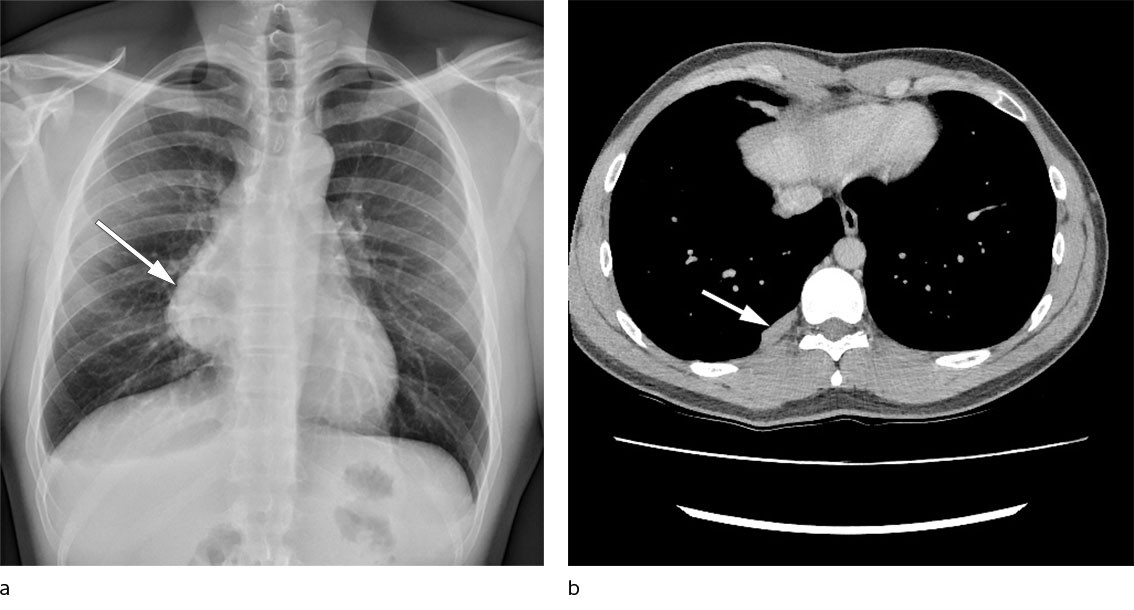

Pasienten var en aldri-røykende mann i 20-årene som hadde barneastma, men som ellers var tidligere frisk. Det aktuelle startet med vedvarende brystsmerter og økende aktivitetsdyspné etter et ubetydelig traume på et treningsstudio. Røntgen toraks viste stor nytilkommen mediastinal oppfylning på høyre side sammenlignet med røntgen tatt fire år tidligere i forbindelse med et annet traume (figur 1a). CT toraks viste en 12 × 9 × 6,5 cm stor tumor i fremre mediastinum, mistenkt å utgå fra thymusrest uten tegn til innvekst i mediastinale strukturer. CT-veiledet biopsi ble vurdert som tymom type B1 - 2. Pasienten ble radikalt operert med sternotomi og tymektomi uten makroskopisk resttumor og uten komplikasjoner.

Pasienten fikk postoperativ strålebehandling. Han ble fulgt opp hvert halvår med CT toraks og kontroll på poliklinikk for lungesykdommer. To år etter operasjonen ble det påvist tre nytilkomne oppfylninger i høyre pleura (figur 1b). Den største var 23 mm og billedmessig lik det opprinnelig ekstirperte tymomet ved sammenligning med preoperativ CT torax. Pleuraoppfylningene hadde moderat økt FDG-opptak (fluordeoksyglukose) på PET-CT. CT-veiledet pleurabiopsi viste funn av cellefattig fibrose og tverrstripet muskulatur.